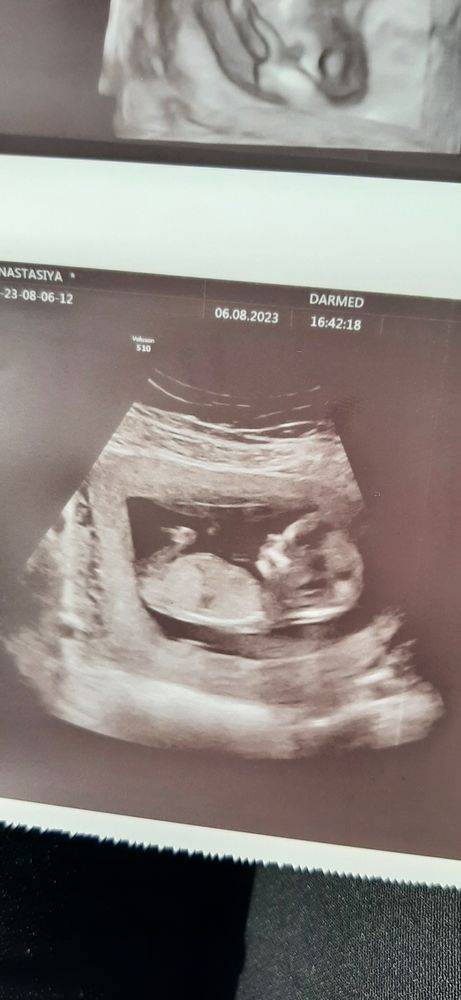

Результаты скрининга на 12-13 неделе: 80% вероятность девочки. Нужна помощь в сравнении снимков!

Девочка. Половой бугорок вниз

Изображение А вот так в 23 недельки ровно )